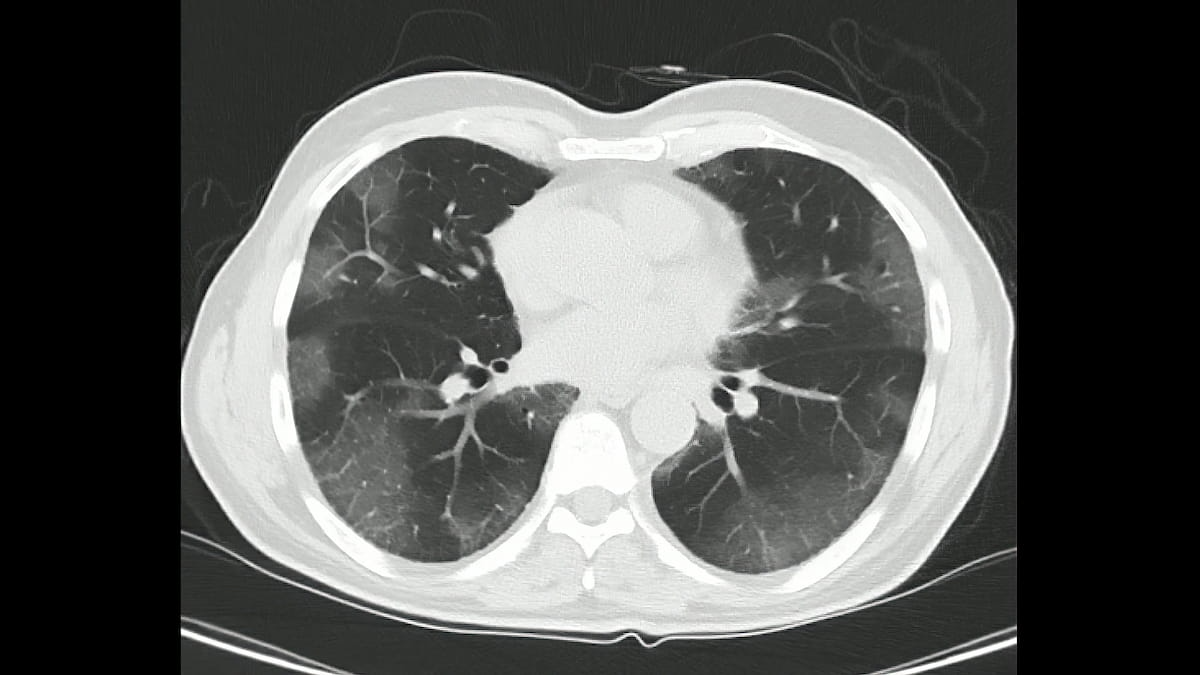

In a large retrospective study of 26,455 participants from the National Lung Screening Trial, low dose computed tomography (LDCT) exams revealed significant incidental findings (SIFs), ranging from emphysema to suspicious lesions, in 8,954 participants.

Over the course of a decade, people with preexisting emphysema who continued smoking had the greatest decline in lung density, according to computed tomography (CT) findings from a study involving over 8,400 total participants and over 4,100 current smokers.